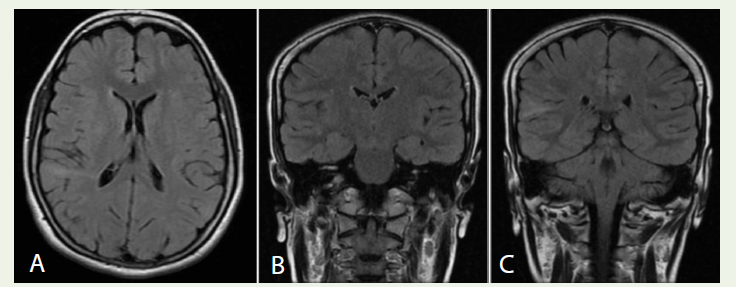

Case 1: A 17-year-old female with focal seizures showed right parietal cortical thickening and a T2-FLAIR transmantle sign on MRI [Figure 1A-C], consistent with focal cortical dysplasia.

was normal. No skin findings or systemic issues.Imaging findings: A 1.5T brain MRI revealed a lesion in the right

parietal cortex. Axial T2-FLAIR images showed subcortical white

matter hyperintensity extending from the cortex toward the lateral

ventricle (the “Transmantle sign” on (Figure1A). Coronal T2-FLAIR

images demonstrated focal cortical thickening and blurring of the

gray–white junction in the right parietal region [Figure 1B], along

with patchy hyperintensity in the right parietal gyrus [Figure 1C].

these features indicate abnormal cortical development.

Diagnosis: Imaging findings are diagnostic of right parietal type

II focal cortical dysplasia.

Figure 1: A: Axial T2-FLAIR MRI showing subcortical white matter hyperintensity extending from the right parietal cortex to the lateral ventricle (Transmantle sign). B: Coronal T2-FLAIR MRI demonstrating cortical thickening and a blurred gray–white matter junction in the right parietal lobe. C: Coronal T2-FLAIR MRI

showing focal hyperintensity in the right parietal gyrus